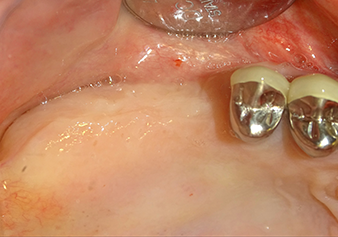

49-летняя пациентка, некурящая и не имеющая ничего примечательного в общей истории болезни, была направлена в нашу хирургическую стоматологическую клинику для хирургического удаления зуба 16 и последующей имплантации. После удаления зуба пациентка перенесла синусит в легкой форме, в результате чего мы сначала выждали шесть месяцев перед проведением операции. Остаточная высота кости при запланированном положении имплантата составляла 3-4 мм (рис. 1 и 2).